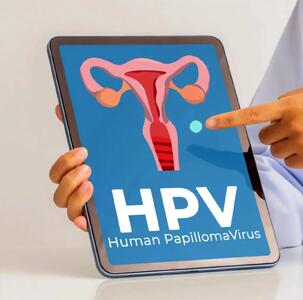

بیماری HPV؛ نحوه انتقال، خطرات، پیشگیری و درمان

در این مقاله، به بررسی نحوه انتقال، خطرات، راهکارهای پیشگیری و درمان HPV میپردازیم و تأثیر رابطه جنسی پرخطر در انتقال این بیماری را به طور تخصصی بررسی میکنیم.

خرید واکسن گارداسیل فقط در بازار سیاه/ همدستی علنی داروخانه و دلالان

برخی از پزشکان متخصص با استفاده از کد ملی بیمارانشان، بدون اینکه آنها درخواستی داشته باشند، نسخه صوری تجویز میکنند و از این طریق، تعداد زیادی واکسن گارداسیل میخرند و به قیمت چندبرابری میفروشند